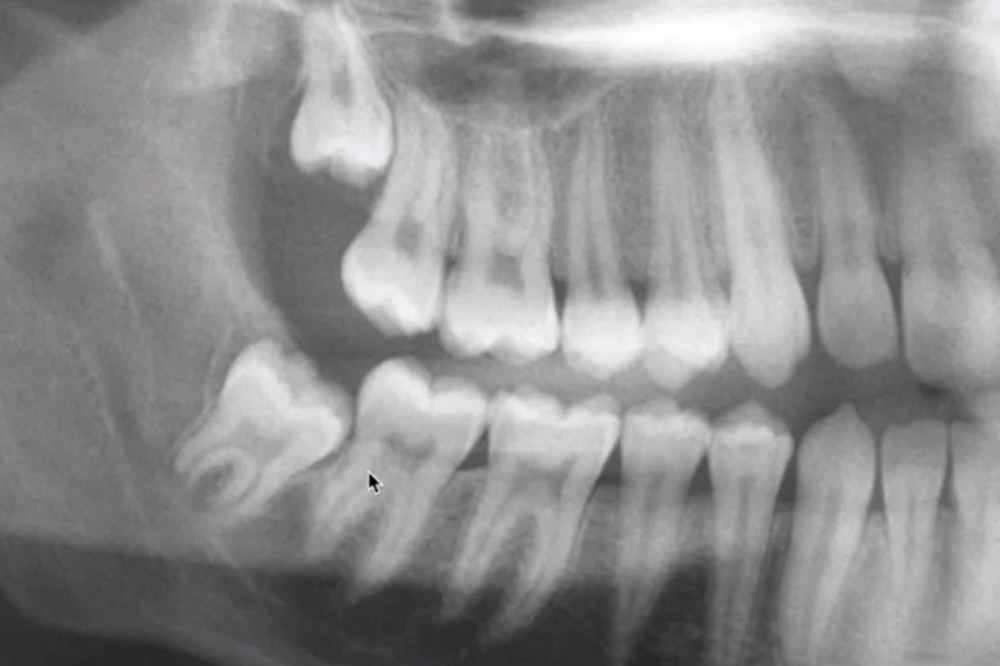

Do I need to have my wisdom teeth removed?

If you’re experiencing pain from a wisdom tooth, have swelling in the gum surrounding the tooth, or the tooth isn’t able to fully emerge into your mouth, it is often necessary to have the wisdom tooth removed.

Not all wisdom teeth require removal. If they are fully erupted into the proper position, they can function normally like other teeth.

However, if the tooth is partially erupted and difficult to clean, then bacteria can accumulate around it, resulting in infection, pain, tooth decay/damage to adjacent teeth, gum disease and cyst formation.